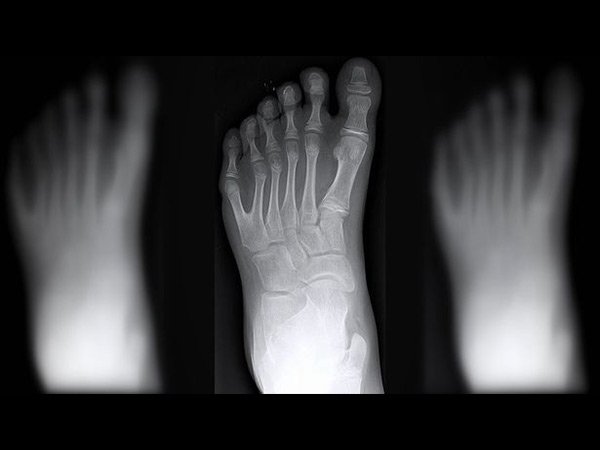

ಈ ಕುಟುಂಬದ ಪ್ರತಿಯೊಬ್ಬ ಸದಸ್ಯನಿಗೂ 12 ಬೆರಳುಗಳು!!

ಕೈ ಮತ್ತು ಕಾಲಿನಲ್ಲಿ ಒಟ್ಟು ಎಷ್ಟು ಬೆರಳುಗಳು ಇದೆ ಎಂದು ಕೇಳಿದರೆ ಆಗ ಬರುವ ಉತ್ತರ 20. ಕೆಲವರಿಗೆ ಒಂದು ಬೆರಳು ಹೆಚ್ಚಿಗೆ ಇರುಬಹುದು. ಆದರೆ ಪ್ರತಿಯೊಬ್ಬ ಮಾನವನು ಒಂದೇ ರೀತಿಯಾಗಿರದೆ ಇಲ್ಲದ ಕಾರಣ ಇದು ಸಹಜವೆನ್ನಬಹುದು. ಮಾನವನ ಗುಣಸ್ವಭಾವದಲ್ಲಿ ಬದಲಾವಣೆಗಳು ಇರುವಂತೆ ದೇಹದಲ್ಲಿನ ಅಂಗಾಂಗಗಳಲ್ಲಿಯೂ ಬದಲಾವಣೆಗಳು ಇರುವುದು. ಕೆಲವರಿಗೆ ಅನುವಂಶಿಯವಾಗಿ ದೇಹದಲ್ಲಿನ ಅಂಗಗಳು ಬಂದಿರುವುದು. ಈ ಲೇಖನದಲ್ಲಿ ಹೇಳಲು ಹೊರಟಿರುವುದು ಬ್ರೆಜಿಲ್ನ ಒಂದು ಕುಟುಂಬದ ಬಗ್ಗೆ ಇಲ್ಲಿರುವ ಸುಮಾರು 14 ಮಂದಿಯ ಕೈ ಮತ್ತು ಕಾಲಿನಲ್ಲಿ ಕ್ರಮವಾಗಿ 12 ಬೆರಳು ಇದೆ. ಇದು ತುಂಬಾ ವಿಚಿತ್ರವೆಂದು ಕಾಣಿಸುವುದಾದರೂ ಸತ್ಯ. ಈ ವಿಶಿಷ್ಟ ಕುಟುಂಬದ ಬಗ್ಗೆ ಮತ್ತಷ್ಟು ತಿಳಿಯಲು ಮುಂದೆ ಓದಿ...

ಈ ಕುಟುಂಬದ ಹೆಸರು ಡಿ ಸಿಲ್ವಾ ಎಂದು. ಕುಟುಂಬದ ವಿಶೇಷತೆಯೆಂದರೆ ಕುಟುಂಬದ 14 ಮಂದಿ ಸದಸ್ಯರು ಹುಟ್ಟುವಾಗಲೇ 12 ಕೈ ಮತ್ತು ಕಾಲಿನ ಬೆರಳುಗಳನ್ನು ಹೊಂದಿದ್ದಾರೆ.

ಅಗ್ರ ಮಾಧ್ಯಮವೊಂದರಲ್ಲಿ ಬಂದಿರುವ ವರದಿಯ ಪ್ರಕಾರ ಇತ್ತೀಚೆಗೆ ಈ ಕುಟುಂಬದ ಜನಿಸಿದ ಸಣ್ಣ ಮಗುವಿನ ಕೈ ಮತ್ತು ಕಾಲಿನ ಬೆರಳುಗಳು 12. ಅನುವಂಶಿಯವಾಗಿ ಬಂದಿರುವ ಈ ಅಸಹಜತೆಯು ಈಗ ಕುಟುಂಬದ ಗುರುತಾಗಿದೆ. ಅಸಹಜತೆ ಬಗ್ಗೆ ಕುಟುಂಬದ ಯಾವ ಸದಸ್ಯನಿಗೂ ಬೇಸರವಿಲ್ಲ.

ಈ ಅನುವಂಶೀಯ ಕಾಯಿಲೆಯು 'ಪಾಲಿಡಕ್ಟೈಲಿ' ಎನ್ನುವ ಪರಿಸ್ಥಿತಿಯಾಗಿದೆ. ಸಾವಿರದಲ್ಲಿ ಒಬ್ಬರು ಇಂತಹ ಪರಿಸ್ಥಿತಿಯಲ್ಲಿ ಹುಟ್ಟುವರು ಎಂದು ಅಧ್ಯಯನಗಳು ಹೇಳಿವೆ.

ಈ ಪರಿಸ್ಥಿತಿಗೆ ವಿವಿಧ ಪರಿವರ್ತನೆಗಳು ಕಾರಣವಾಗುತ್ತದೆ. ಆದರೆ ಕೈ ಮತ್ತು ಕಾಲಿನಲ್ಲಿ ಹೆಚ್ಚುವರಿ ಬೆರಳು ಪಡೆಯುವುದು ಜಿನ್ ಗಳಲ್ಲಿ ಆಗಿರುವ ಕೆಲವು ಪಲ್ಲಟಗಳನ್ನು ಸೂಚಿಸುವುದು. ಸಾಮಾನ್ಯವಾಗಿ ಇದರಿಂದ ಹೆಚ್ಚುವರಿ ಬೆರಳುಗಳು ಬರುವುದು.

ವೈದ್ಯರು ಹೇಳುವ ಪ್ರಕಾರ ನಿಮ್ಮ ತಂದೆ ಅಥವಾ ತಾಯಿಗೆ ಹೆಚ್ಚುವರಿ ಬೆರಳುಗಳಿದ್ದರೆ ನಿಮಗೂ ಹೆಚ್ಚುವರಿ ಬೆರಳು ಬರುವ ಸಾಧ್ಯತೆಯು ಶೇ.50ರಷ್ಟಿರುವುದು.